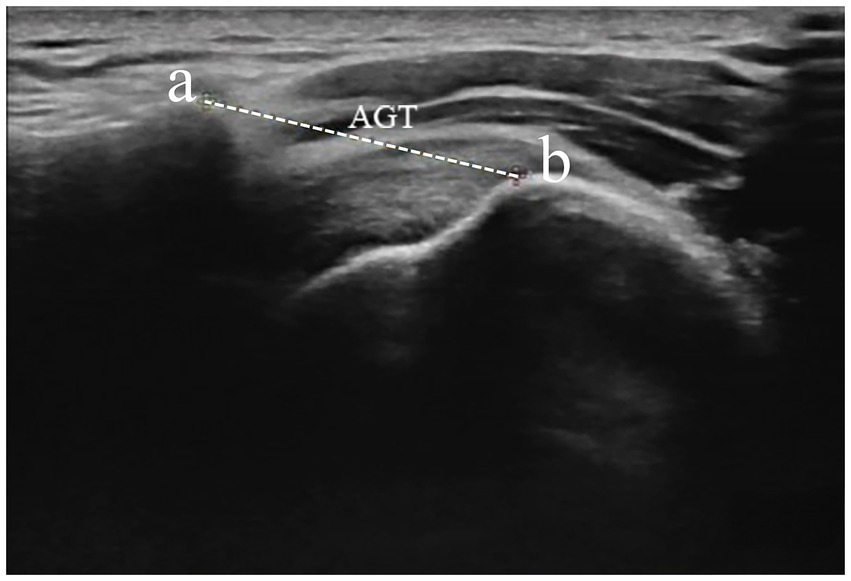

In the evaluation of AGT during ultrasound procedures (RS80A, Samsung, Korea), the research included 22 healthy participants based on the informed consent of each participant. The participants’ posture required is consistent with the posture of radiographic measurement of AHD. The transducer was positioned at the anterior edge of the shoulder within the coronal plane (Figure 4). After the acromion and greater tuberosity of the humerus appeared on the screen, the image was captured, allowing for the measurement of the shortest distance between the acromion and the greater tuberosity (18) (Figure 5). Data from bilateral AGTs were documented, and the ratio of the bilateral distances was calculated (Left/Right). Two separate measurements were utilized to evaluate reliability. These procedures were performed by a single ultrasonologist.

Figure 5

Measurement of AGT distance from the lateral border of the acromion and the nearest superior margin of the greater tuberosity. Dotted caliper represents AGT distance. AGT acromion–greater tuberosity. a—acromion, b—greater tuberosity.